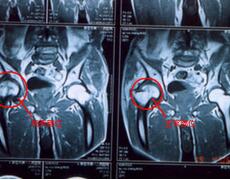

Computed Tomography 简称CT,自1970年首先由Housebield临床应…… 【详情】